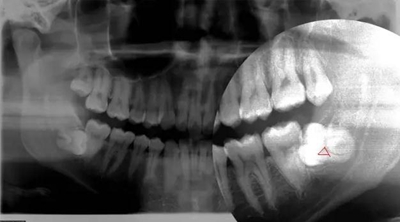

智齒水平阻生(長(zhǎng)橫過(guò)來(lái)了),影響前面牙齒或者致前面牙齒擁擠不齊

1.jpg